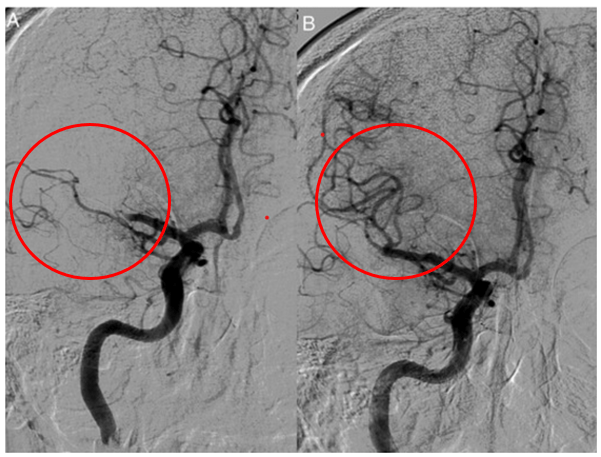

Si une hémorragie est mise en évidence, le diagnostic d’AVC hémorragique est posé et une prise en charge spécifique est initiée. Si aucun saignement n’est visible, l’hypothèse d’un AVC ischémique aigu est privilégiée. Dans ce cas, une angiographie par scanner (angio-TDM) peut être réalisée pour visualiser les artères cérébrales et repérer une occlusion d’un gros vaisseau (Figure 4).

Figure 4 : Angiographie carotidienne avant et après thrombectomie par cathéter dans un accident vasculaire cérébral aigu de la circulation antérieure.

(A) Occlusion thrombotique de l’artère cérébrale moyenne à l’admission.

(B) Artère cérébrale moyenne largement perméable (presque normale) après thrombectomie (Source : P. Widimsky et al.) [25]

L’injection d’un produit de contraste permet de dresser une cartographie précise du réseau vasculaire. L’imagerie vasculaire complète ce bilan en explorant les artères intracrâniennes et cervicales afin de localiser une sténose, une dissection ou une occlusion.